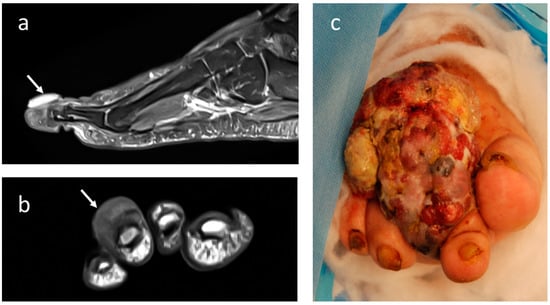

4.3. Synovial Sarcoma

4.4. Clear-Cell Sarcoma